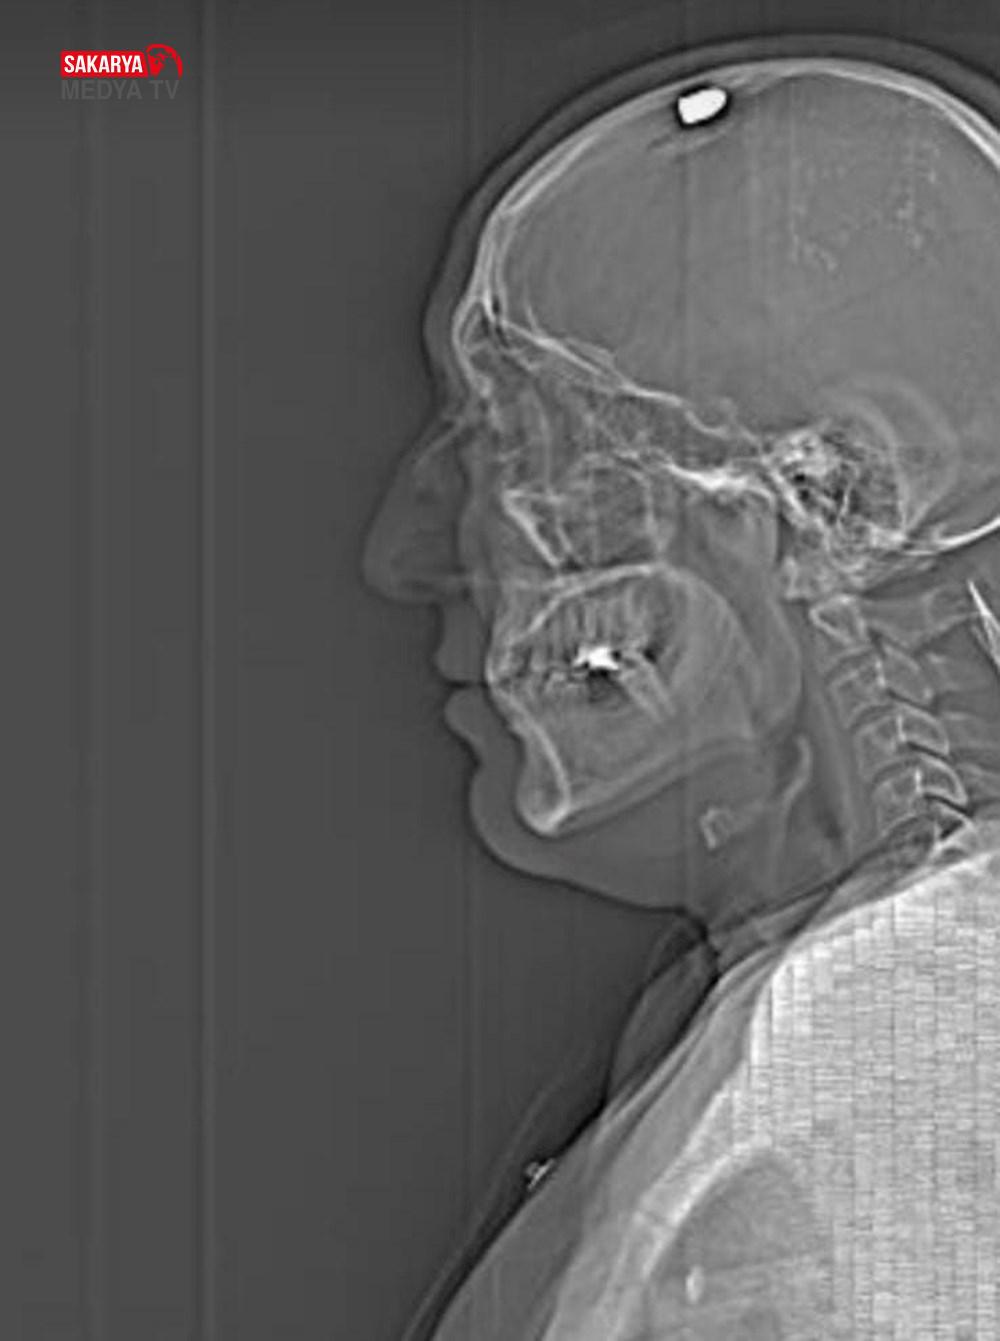

Silahla başından vuruldu, ölü taklidi yapıp kurtuldu!

Ankara’da bir kişi silahlı hücumdan meyyit taklidi yaparak kurtuldu. Olay, 18 Şubat günü Çankaya’da meydana geldi. Fırat Sucuğ, kuzeni Erdi S. (33) ile birlikte, toplumsal medyada tartıştığı Alper A. (28) ile görüşmek için onun akrabası Savaş Koç’un iş yerine gitti. Restoranda kurye olan Savaş Koç, akrabasının yerini söylemeyince tartışma çıktı. Savaş Koç, aracının bagajından av tüfeğini çıkardı. Erdi S., tüfeği almak isterken Fırat Sucuğ da tabancasını çıkarıp başına bir el ateş etti. Ağır yaralanan Savaş Koç, hastaneye kaldırıldı. Koç, 1 ay süren tedaviyle sıhhatine kavuşarak taburcu edildi.

Gözaltına alınıp tutuklanan Fırat Sucuğ ile tutuksuz Erdi S. hakkında ise öldürmeye teşebbüs cürmünden müebbet mahpus cezası talebiyle 35. Ağır Ceza Mahkemesi’nde dava açıldı. Sanıkların yargılaması devam ederken, dava evrakına giren olay anına ait güvenlik kamerası imajı ortaya çıktı. Görüntüde taraflar ortasındaki arbede ve Fırat Sucuğ’un Savaş Koç’u başından vurması yer aldı.

O sırada iki kişi geliyor bunlar. Kapının önünde benim üzerime geldiler. O sırada Fırat, belinden silahı çıkardı ve bana doğrulttu. İki sefer tetiğe bastı; fakat ateş almadı.

Sonra Fırat silahını düzeltmişti. O sırada ben can havliyle kendimi müdafaaya çalışıyordum. En sonunda beni vurdu.” “Tekrar bir daha beni öldürmesin diye ben meyyit numarası yaptım, hareketsiz durdum. Lakin her şeyi duyuyordum. Yani ben adaletin şu an için yerini bulmasını istiyorum.

Hak ettikleri cezayı almalarını istiyorum. Şans yapıtı yaşıyorum şu an. O kurşun bir santim daha içeri girse şu an ayakta olmayabilirdim.” Sanığın tutukluğunun devamına karar veren mahkeme, eksikliklerin giderilmesi için davayı erteledi.